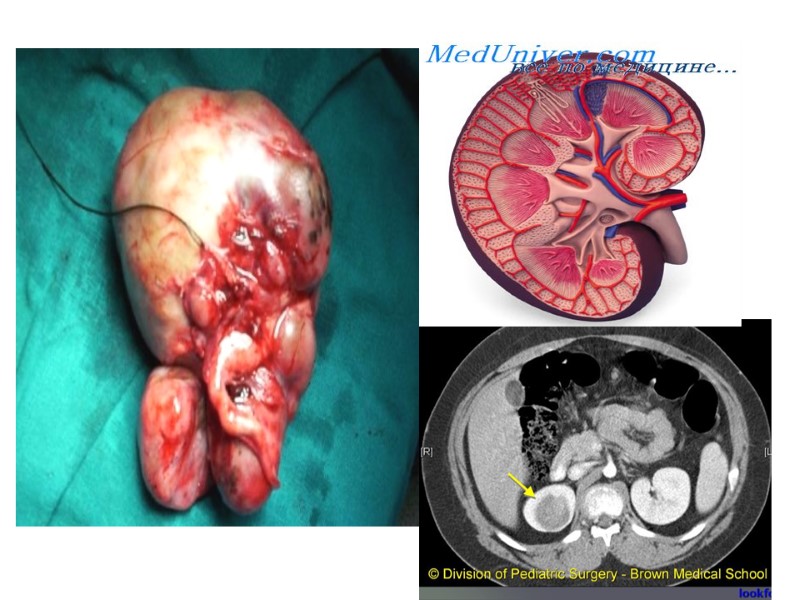

НЕФРОБЛАСТОМА (ОПУХОЛЬ ВИЛЬМСА) Связана с нарушением эмбриогенеза почки, ключевая роль в патогенезе отведена генетическим нарущениям. За развитие ОВ ответственны нарушения в нескольких генах – WT1,WT2,WT3. Роль гненетических факторов в развитии ОВ подтверждает также ее частое сочетание с пороками развития других органов и систем: аномалии МВП, аниридия,врожденная гемигипертрофия, синдром Беквитта-Видеманна. При указанных аномалиях рекомендуется проводить УЗИ почек каждые 3 мес до достижения 7-летнего возраста.

Нефробласто́ма (опухоль Вильмса) — высокозлокачественная эмбриональная опухоль, происходящая из развивающихся тканей почек. Заболевание является наиболее частым злокачественным новообразованием мочеполового тракта у детей. Наиболее часто встречается в возрасте до 5 лет с одинаковой частотой у мальчиков и девочек. Опухоль Вильмса часто сочетается и с врождёнными аномалиями развития.

СИМПТОМАТИКА Клиническая картина ОВ зависит от стадии заболевания, наличия метастазов и возраста пациента. На ранних стадиях заболевания клинические проявления опухоли скудные и чаще всего выражаются в слабости, недомогании, похудании, снижении аппетита, периодическом субфебрилитете, умеренной анемии, повышении СОЭ. На поздних стадиях ОВ наиболее специфическим признаком является пальпируемое объемное образование в животе. Иногда оно выявляется матерью или врачом при обычном осмотре ребенка, не предъявляющего никаких жалоб и хорошо себя чувствующего. При пальпации опухоль чаще всего плотная и гладкая, реже бугристая. Опухоль может фиксироваться к окружающим структурам и не смещаться при пальпации.

Боли не характерны для ОВ, отмечаются обычно у детей с большой опухолью. Причиной болей служат либо давление на окружающие органы, либо прорастание опухоли в диафрагму, печень или забрюшинную клетчатку. Гематурия не является частым симптомом ОВ. Макрогематурия имеет место примерно у 10-12% детей с ОВ. Микрогематурия наблюдается несколько чаще. Умеренное повышение АД отмечали у 60% больных. При этом систолическое давление обычно находится в пределах 110-140 мм рт ст, а дистолическое – 90-100 мм рт ст. Метастазирование ОВ происходит гематогенным и лимфогенным путем. Наиболее частая локализация метастазов – легкие, затем печень, головной мозг, кости, противоположная почка.

Лечение опухоли Вильмса Лечение опухоли Вильмса нужно начинать сразу посте того, как установлен диагноз. Наилучшие результаты показывает комбинированная терапия, то есть сочетание хирургического вмешательства с лучевой и химиотерапией. Операция при опухоли Вильмса заключается в удалении первичного опухолевого очага. С этой целью проводится либо резекция почки, либо ее удаление (нефрэктомия). Одновременно с этими вмешательствами производится удаление одиночных метастазов (при их наличии): резекцию печени или легкого. Лучевая терапия при опухоли Вильмса проводится по различным схемам. Она применяется как до операции, так и после нее, а также и во время операции. Кроме того, лучевая терапия используется и при поздних стадиях опухоли, когда далеко процесс защел слишком далеко и выполнить операцию представляется невозможным.

Диагностика Основывается на данных клинического, ультразвукового исследований, компьютерной и магнитно-резонансной томографии, лабораторной диагностики.